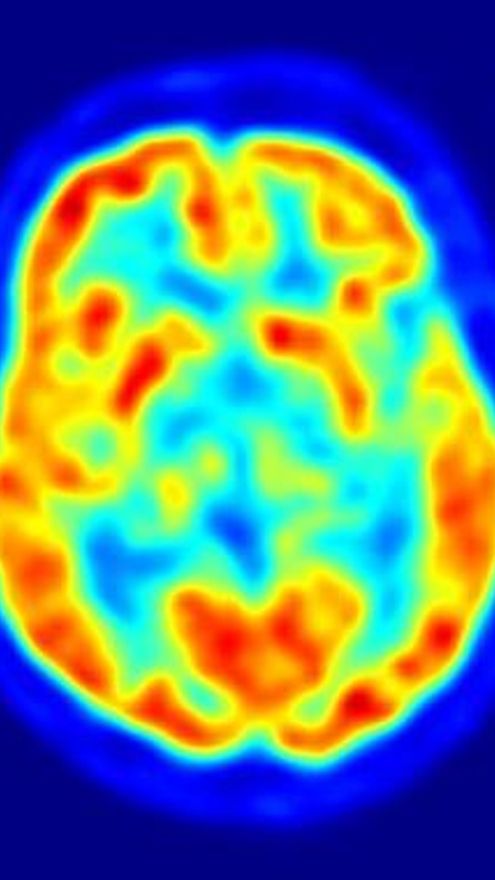

Un nuevo estudio ha desvelado una relación entre una proteína -que puede modificar el metabolismo celular en el cerebro- y la susceptibilidad a las convulsiones. La investigación, publicada en 'Neuron', podría conducir al desarrollo de nuevos tratamientos para la epilepsia.

La epilepsia es un trastorno caracterizado por convulsiones, y una actividad eléctrica anormal del cerebro. Algunos casos de epilepsia son resistentes a los tratamientos farmacológicos tradicionales, pero pueden mejorar mediante una dieta cetogénica -este tipo de dieta, que es muy baja en azúcares y alta en grasas, fuerza a las neuronas a cambiar su combustible habitual, la glucosa, por un tipo de subproducto de la grasa, llamado cuerpo cetónico.